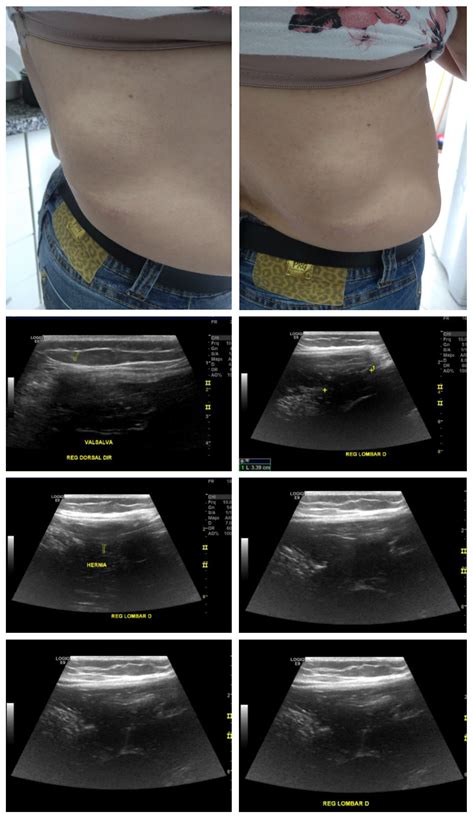

During your consultation, a doctor will likely perform a physical examination, palpating the area to check for firmness, tenderness, or reducibility (whether the bulge can be pushed back in). Depending on their findings, they may order imaging studies such as an ultrasound, CT scan, or an endoscopy to visualize the internal structures and confirm the diagnosis.